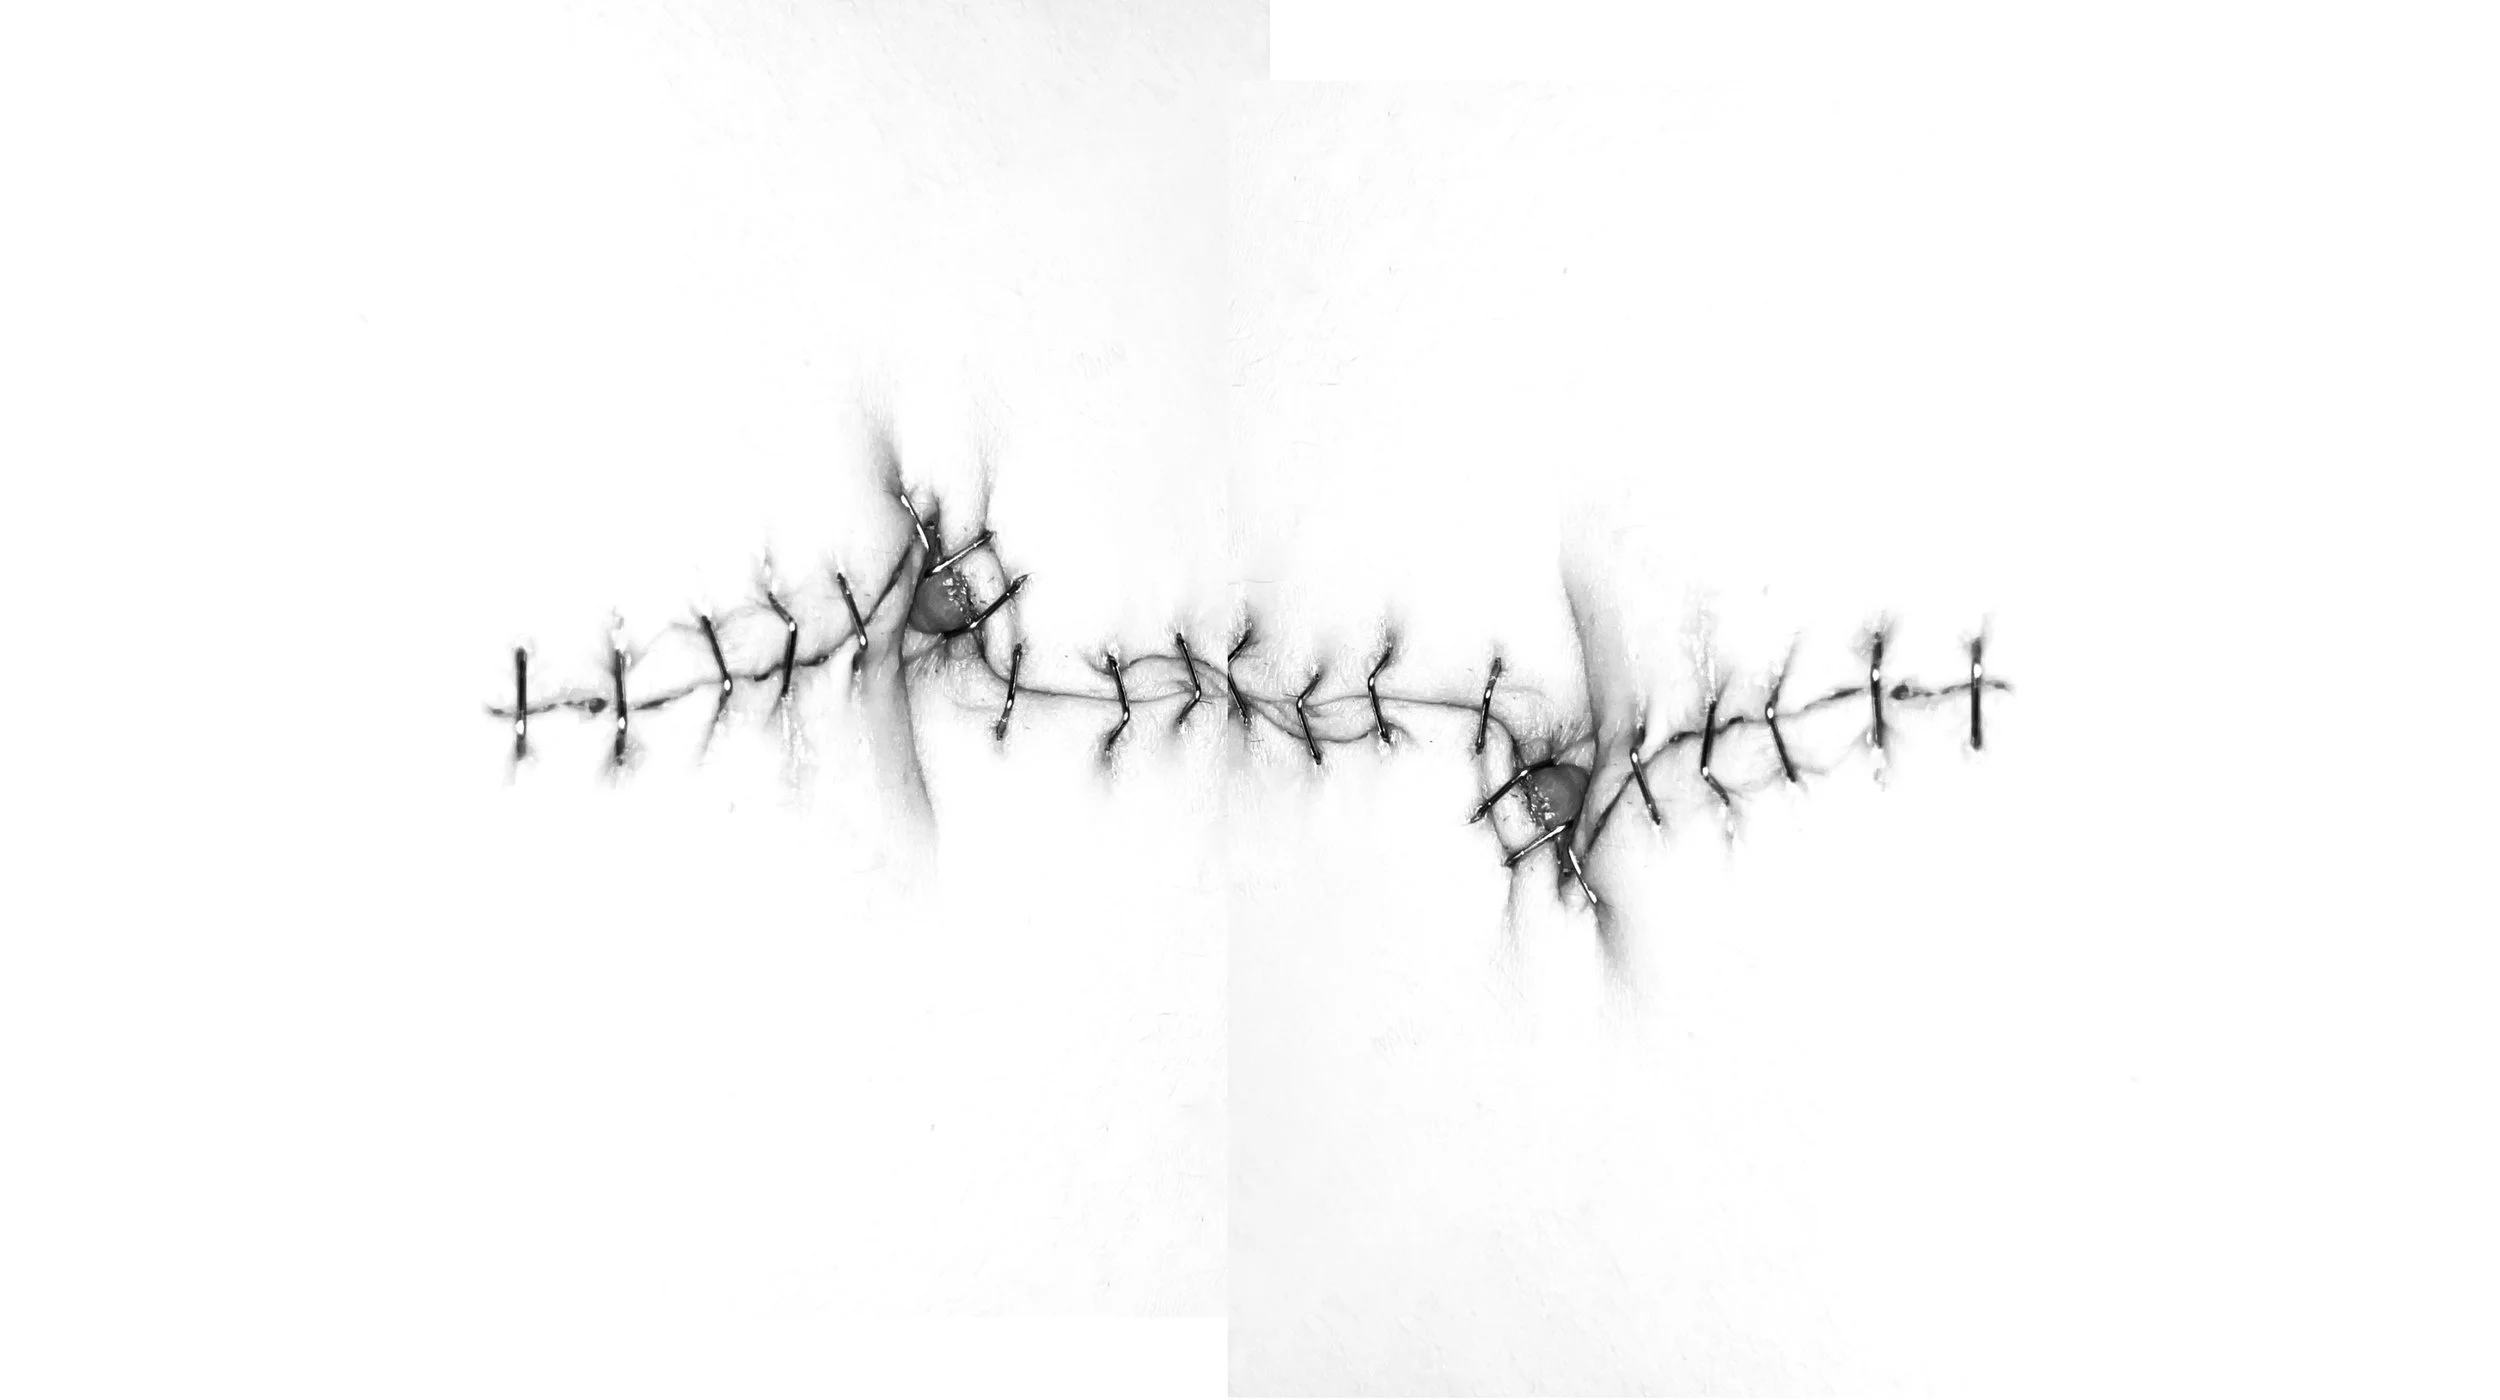

Through my work I seek to dissolve the boundaries between film and photography, the physical and the energetic body, between the visible and what lies beneath.

Nestled at the heart of artistic expression, my photography studio is a sanctuary where beauty, nature, and spirituality converge, offering an unparalleled journey through the lens of exquisite craftsmanship. With an unwavering dedication to capturing humanity’s delicate existence, I invite you to experience my artistic world of visual storytelling where every frame is a bridge between the spiritual and the earthly.